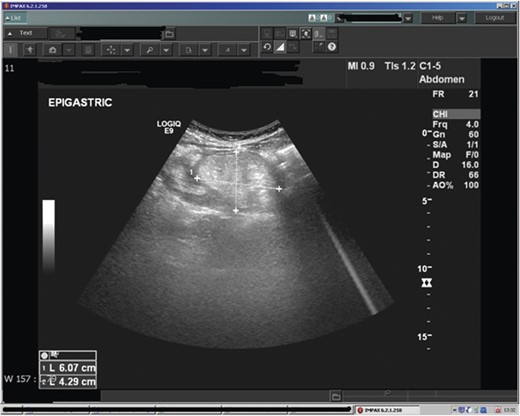

Abdominal ultrasound demonstrated a bowel-related mass lesion in the epigastric region (Fig. 1). Computed tomography (CT) scan of the abdomen and pelvis revealed a 3 × 6 cm fatty ovoid lesion within the transverse colon resulting in intussusception (Fig. 2). Colonoscopy showed an abnormal dusky grey lesion occupying most of the lumen in the distal transverse colon. There were two ulcerated areas on the front of the lesion, most likely the leading point of the intussusception. A laparotomy was performed. Intussusception of the transverse colon was found, for which an extended right hemicolectomy was performed (Fig. 3), with ileo-transverse colon anastomosis and defunctioning loop ileostomy. The patient had an uneventful postoperative recovery and returned later for reversal of his loop ileostomy. The histopathology report confirmed a 6 × 4.5 cm submucosal lipoma acting as a leading point for the intussusception. There was no evidence of malignancy.

Ultrasound of the abdomen demonstrating a bowel related mass lesion in the epigastric region.